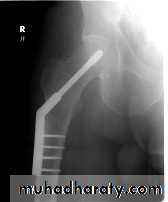

INTERNAL FIXATION

Indications

advantages